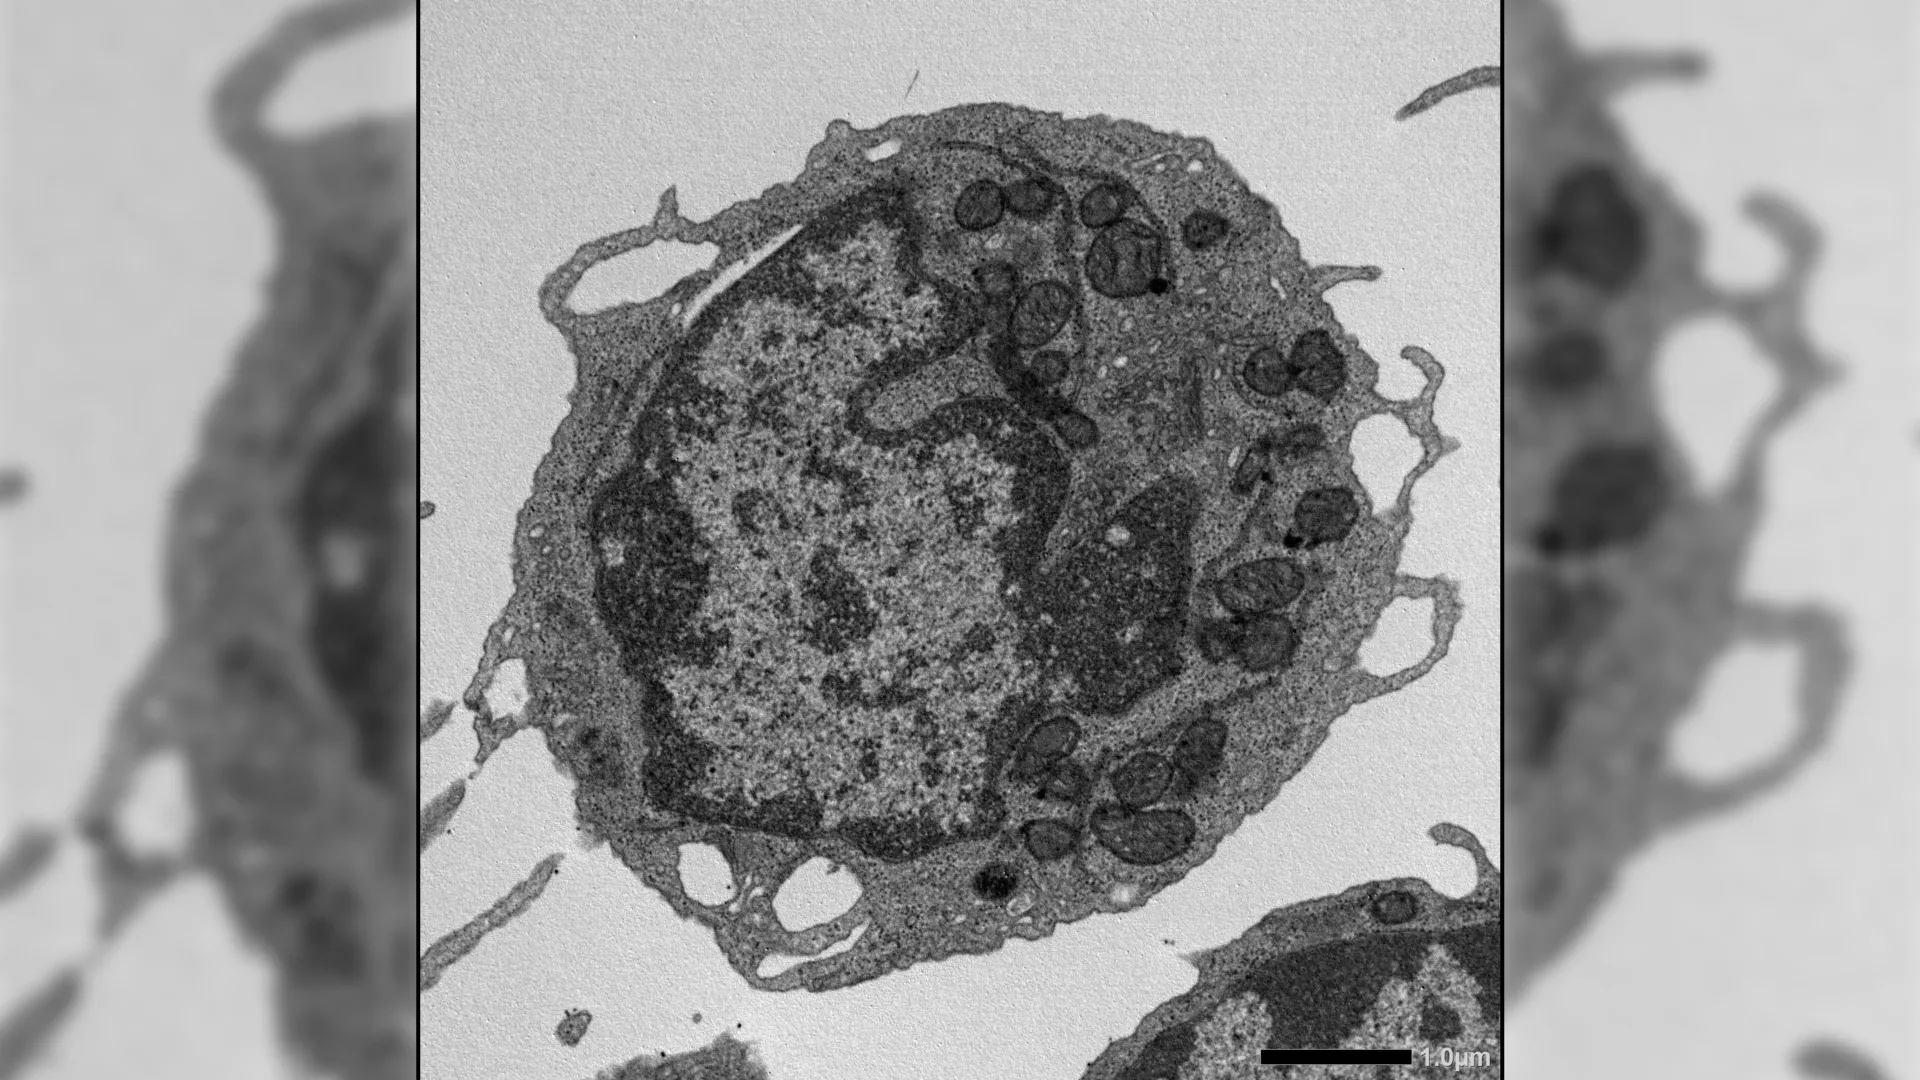

As people get older, their blood and immune systems gradually lose strength. A major reason is the decline of hematopoietic stem cells (HSCs), which are responsible for producing all types of blood cells. Under healthy conditions, these stem…